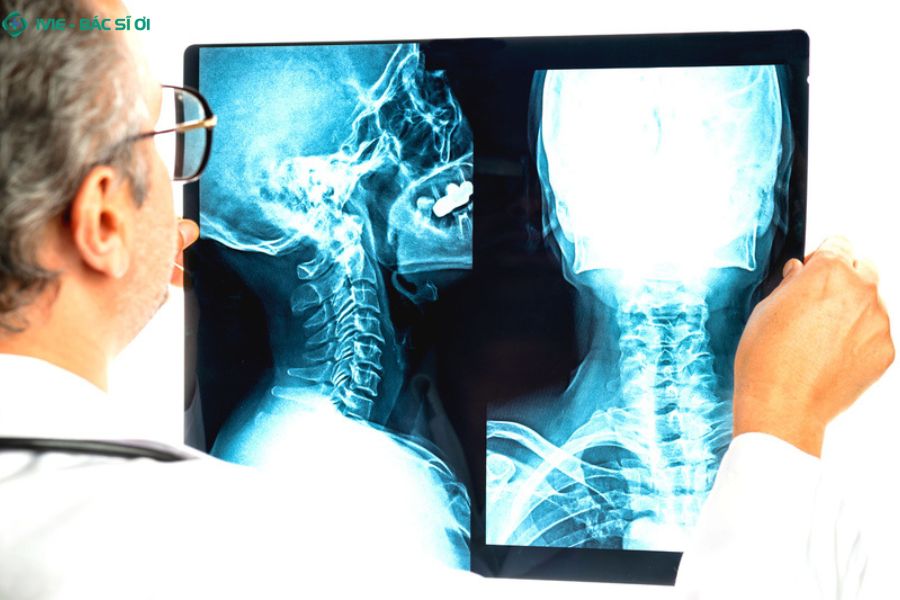

Cách chẩn đoán đau cổ vai gáy bên trái

Phương pháp chẩn đoán đau cổ vai gáy bên trái

Khi thăm khám, bác sĩ sẽ kiểm tra tình trạng cổ và vai của bạn, đánh giá khả năng cử động, vị trí đau, sưng và hỏi về tiền sử bệnh lý hoặc thói quen sinh hoạt. Dựa trên kết quả khám ban đầu, bác sĩ có thể chỉ định thêm các xét nghiệm hoặc chụp chiếu để xác định chính xác nguyên nhân gây đau. Một số phương pháp thường được sử dụng gồm:

Chụp X-quang: Giúp quan sát rõ cấu trúc xương ở vùng cổ và vai.

Chụp MRI (cộng hưởng từ): Cho hình ảnh chi tiết của cả xương và mô mềm như cơ, dây chằng, đĩa đệm.

Chụp CT (cắt lớp vi tính): Cho hình ảnh mặt cắt ngang của vùng cổ, giúp phát hiện tổn thương sâu bên trong.

Nhờ đó, bác sĩ có thể xác định nguyên nhân cụ thể và đưa ra hướng điều trị phù hợp nhất.